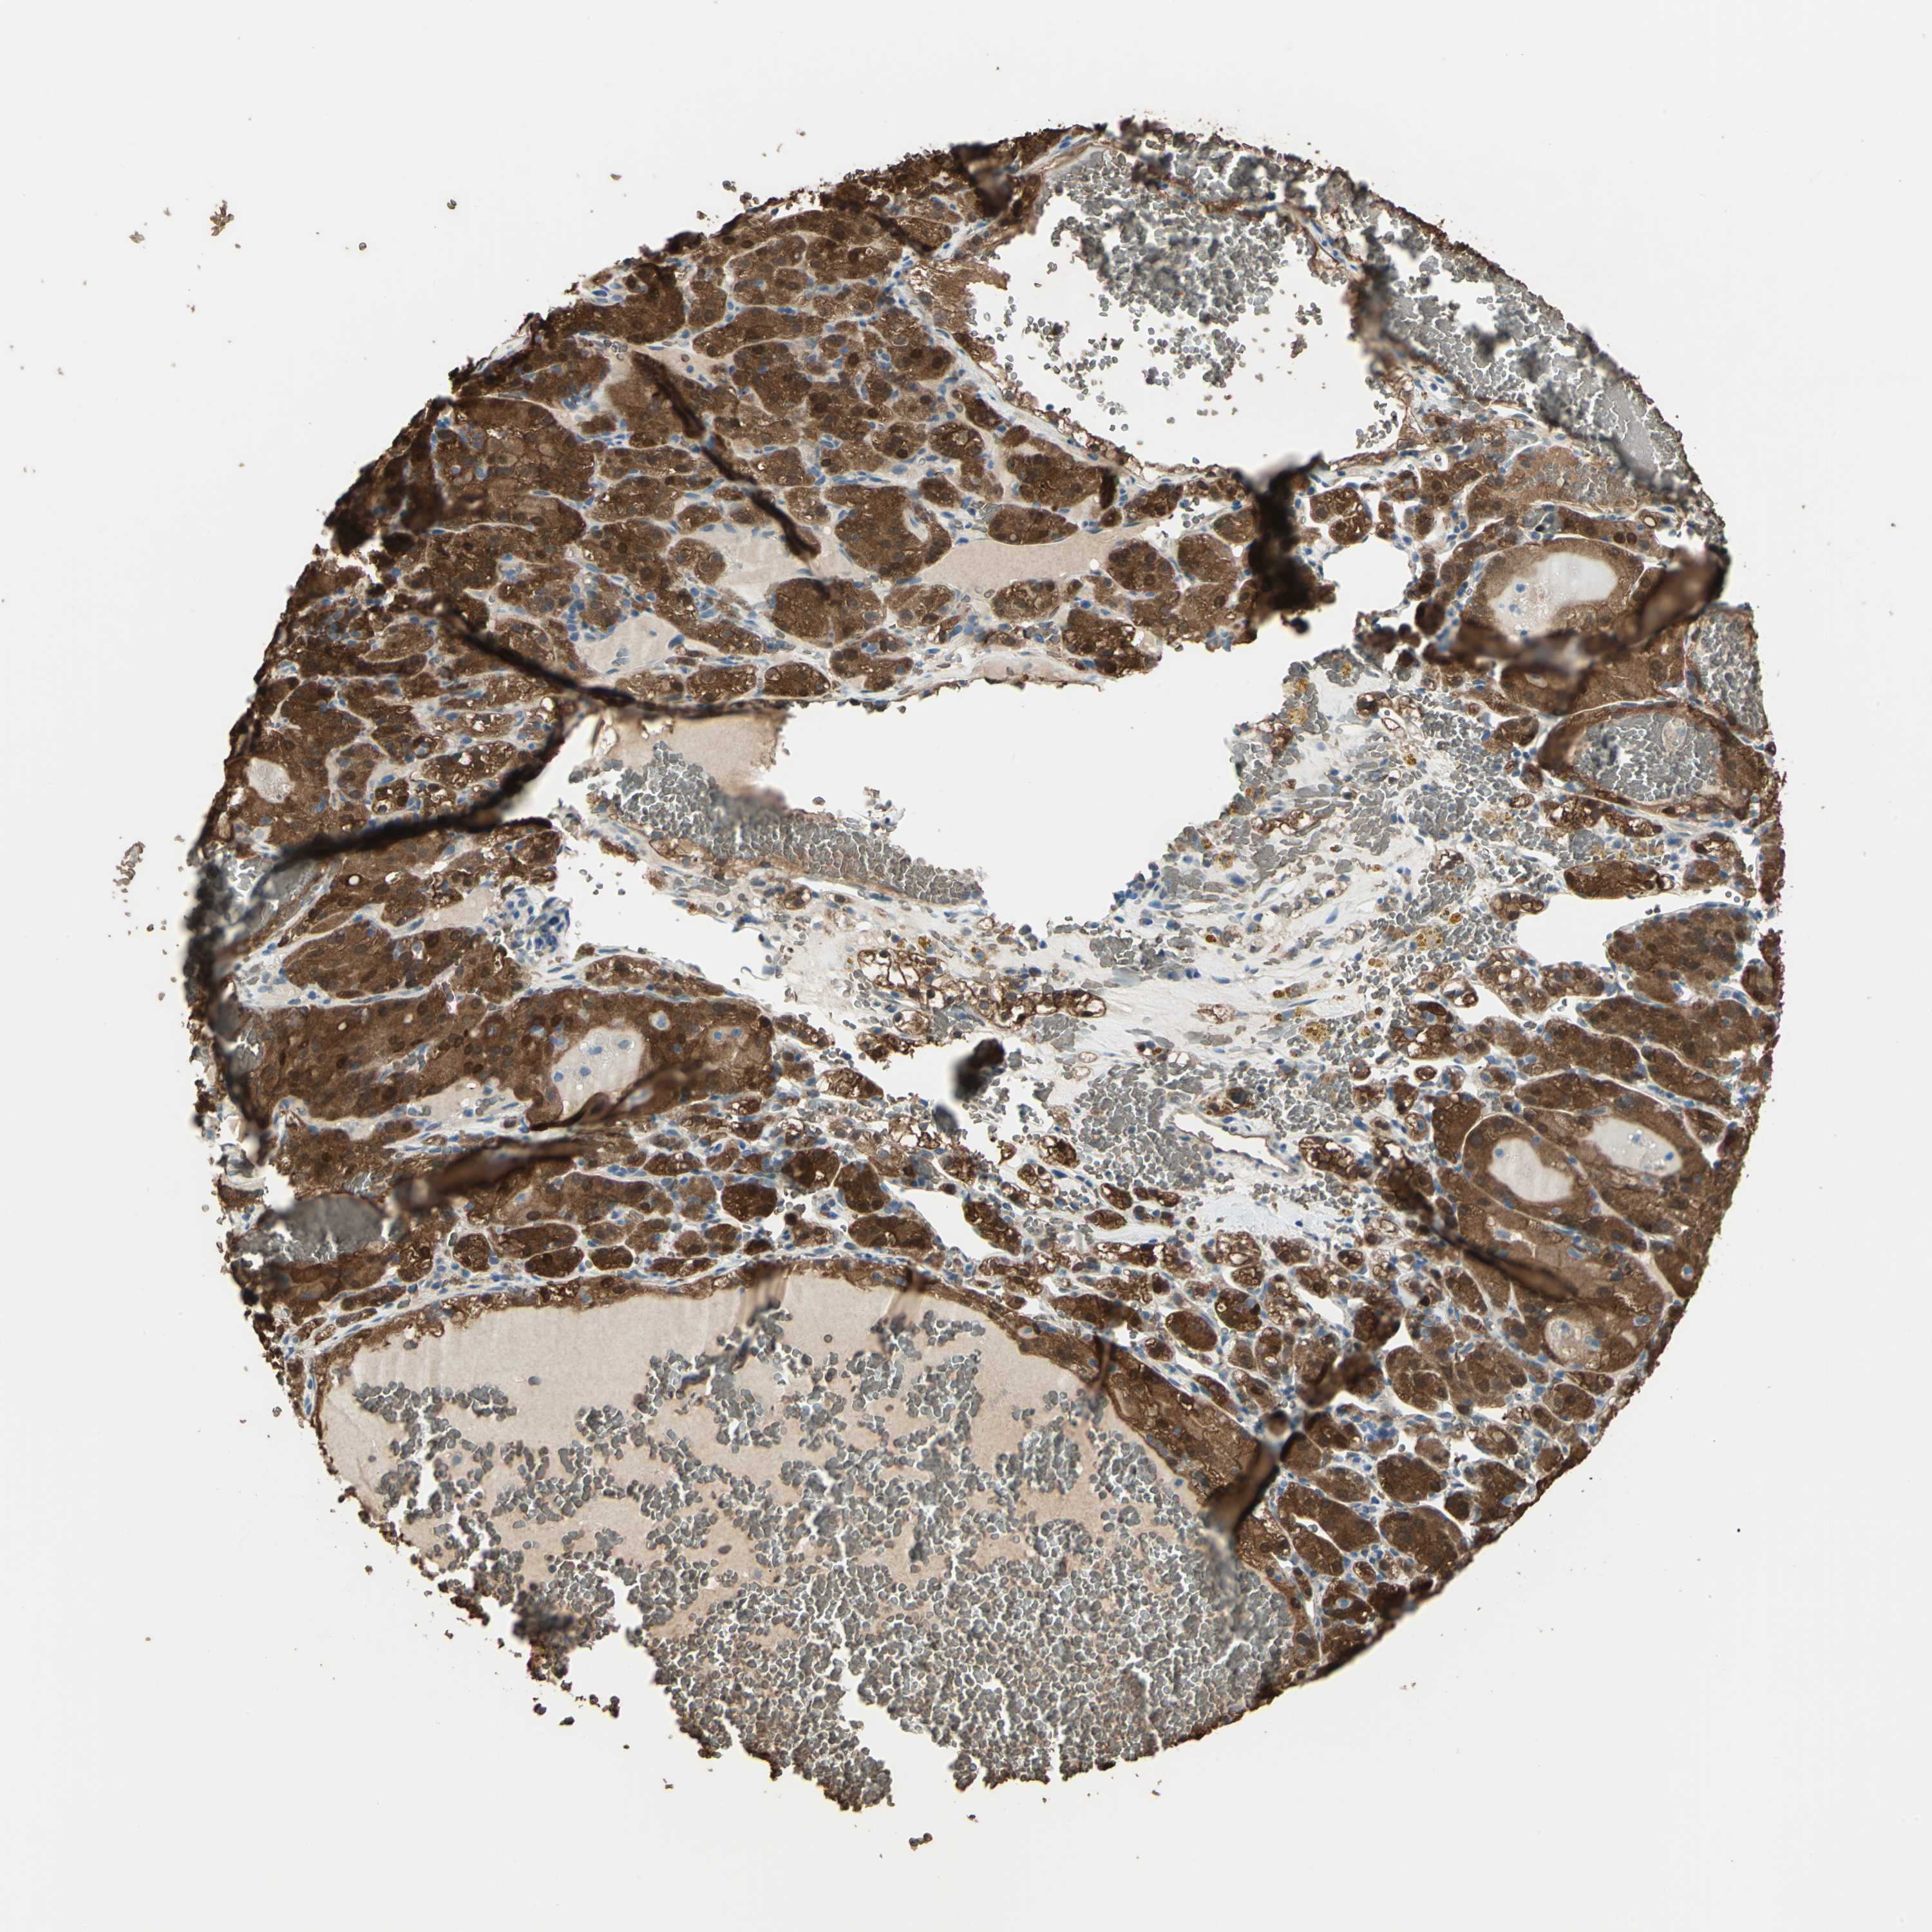

CANCER RENAL CANCER Show tissue menu

KICH TCGA KIRC TCGA KIRC VALIDATION KIRP TCGA PROTEIN RCC CPTAC PROTEIN EXPRESSION

Renal cancer

Kidney chromophobe